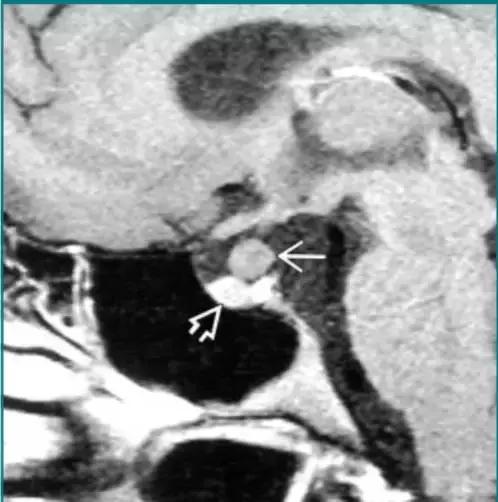

Rathke裂囊肿